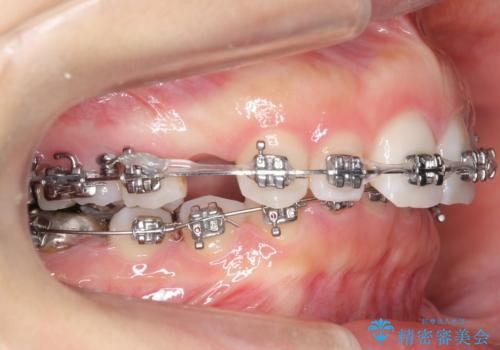

- 矯正装置

- メタル装置

- 治療計画

- 出っ歯を主訴に来院。

かみ合わせが深く、治療に時間がかかりました。

上顎2番は矮小歯だったのをセラミックで被せています。